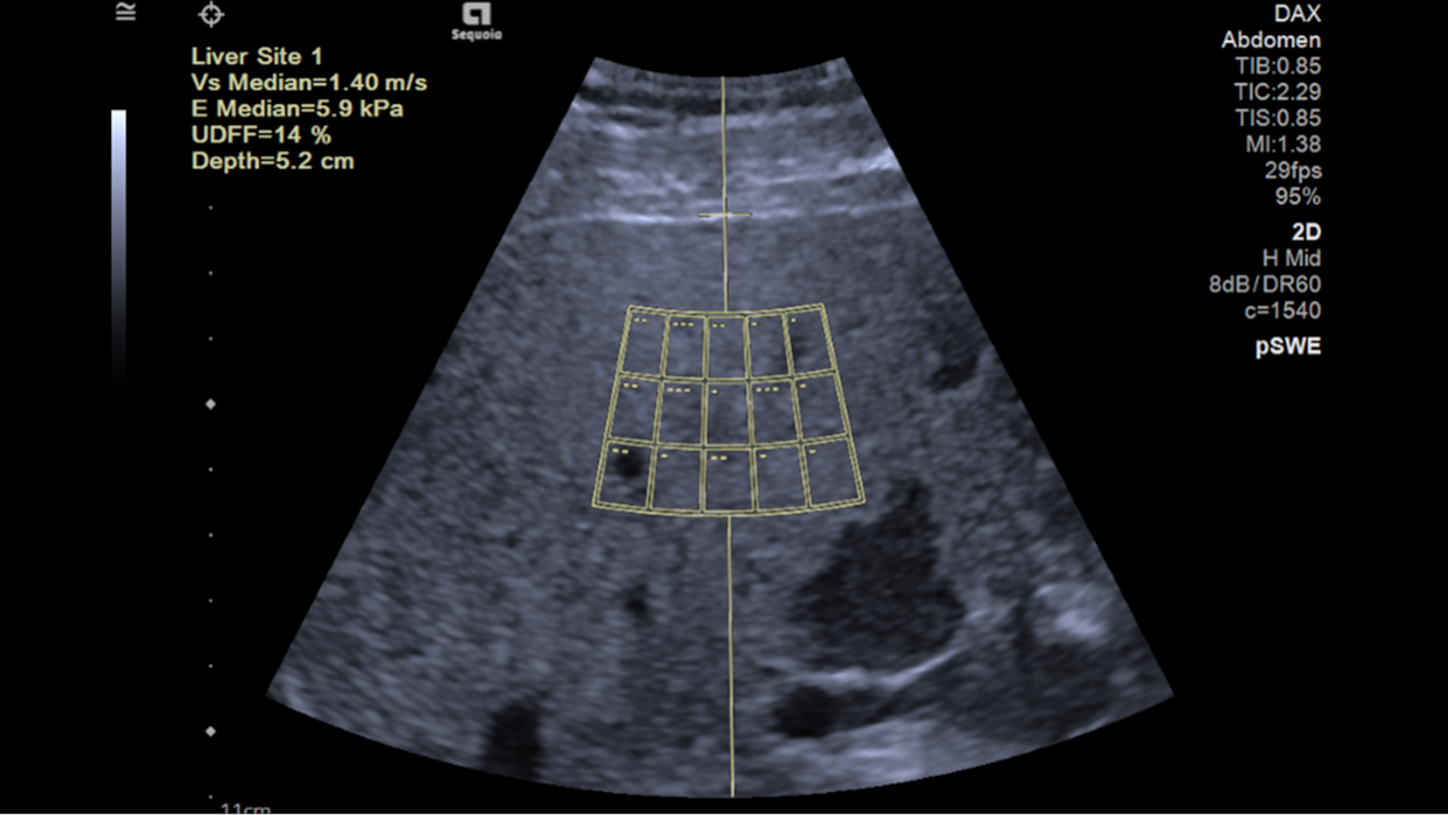

Die Scherwellen-Elastographie

Die Scherwellen-Elastographie misst die Steifigkeit der Leber: Je stärker die Fibrose, desto weniger elastisch das Gewebe – und desto schneller breiten sich Scherwellen aus. Das Ergebnis wird in Meter pro Sekunde (m/s) und in Kilopascal (kPa) angegeben.

Auto pSWE der Leber